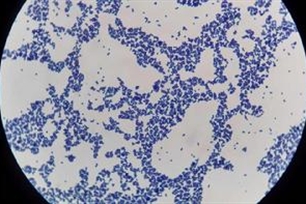

- 一种微生物。属革兰氏阳性球菌,通常聚集成串如葡萄状,故称为「葡萄球菌」。分布极广,在人类或动物的黏膜及皮肤上均可见。其发病率较肺炎球菌或滤过性毒为低,大都发生于乳儿时期。一旦感染即不易治疗,且有脓胸并发症,会威胁生命安全,是所有肺炎中最可怕的病原菌。此病多由于吃下腐败的乳制品或肉类所引起。

【葡萄球菌】 图片鉴赏